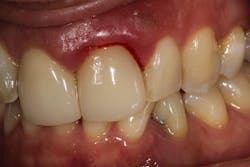

No. 5: Healing time after a dental cleaning

After a dental cleaning, patients may experience soreness and slight bleeding of the gums when brushing for a few days (24–48 hours), but after four weeks the bleeding should stop. If not, fractured calculus may be present under the gums. Explain to patients that they may need see a periodontist (a gum disease specialist) for more advanced periodontal treatment.